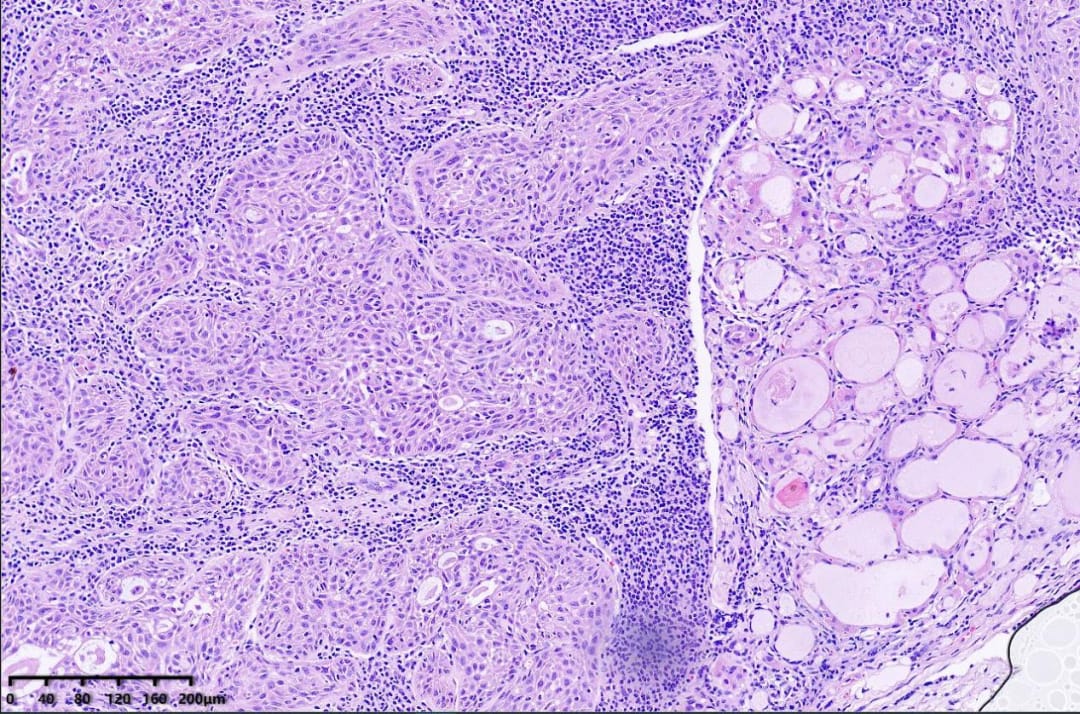

- 镜下所见: 显微镜下可见肿瘤组织呈条索状、巢团状、实片状排列于纤维间质中。肿瘤细胞胞浆丰富,嗜酸性,可见细胞间桥和核深染,核分裂象活跃。部分癌巢周边细胞呈栅栏状排列,局部中央形成角化珠。周围甲状腺组织伴有大量淋巴细胞浸润,呈桥本甲状腺炎改变。

低倍镜,右侧为甲状腺组织伴淋巴细胞浸润,左侧为纤维间质内见肿瘤组织浸润性生长

镜下可见肿瘤细胞呈实性巢状、条索状排列,部分癌巢周边细胞呈栅栏状排列,可见细胞间桥、角化珠和单个细胞角化。肿瘤细胞胞质嗜酸性,核深染,核分裂象多见。间质常伴有纤维组织增生和淋巴细胞浸润。免疫表型上,肿瘤细胞通常表达PAX8、CK19、CK-H、TTF-1、CyclinD1,以及鳞状细胞标记物CK5/6、p40、p63。大部分病例可检测到BRAF V600E突变。分子遗传学方面,TP53及BRAF V600E突变是甲状腺鳞状细胞癌的常见特征。